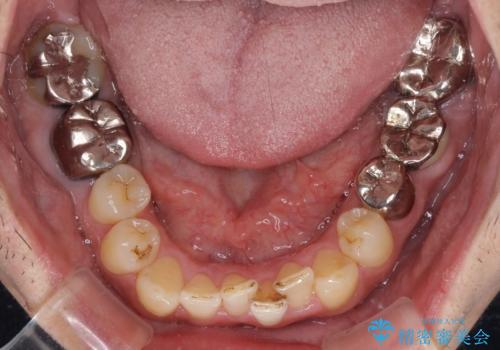

- 近医にてブリッジ治療を行った歯が痛くてたまらないとのことで来院された患者様です。

診察を行ったところ、奥の土台になっている歯は神経組織が失活しており、根尖部に病変があり、そこが原因で痛みを生じている状態でした。

根管治療を行うためにブリッジを除去したところ、むし歯が歯肉の奥深くにあまで及んでいたため、歯周外科処置によりむし歯が歯肉縁より浅い位置へと改善することとしました。

ここまでの治療を提案したところで、折角なのでしっかり治療を行いたいとのことで、前歯のデコボコやクロスバイトを改善するための矯正治療を行うこととしました。

まずは奥歯の痛みを改善し、その後矯正治療を行い、最後にオールセラミックブリッジによる補綴治療を行うこととしました。